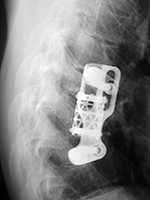

Harms vertebral cage (AP view) |

Harms vertebral cage (lateral view) |

There is a vertebral cage and side plate and screws in the lower thoracic spine for treatment of a spinal tumor. |